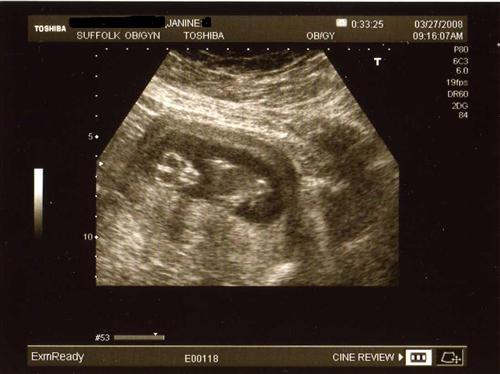

I wanted to share my 12 week sono pics that I had yesterday. Our little one was quite active, as I had a sugery cereal in the morning. Baby was rolling and waving, showing us all five fingers and was rubbing his/her eyes like it just woke up. They said baby looks good and healthy so far.

Alien baby-facing us directly